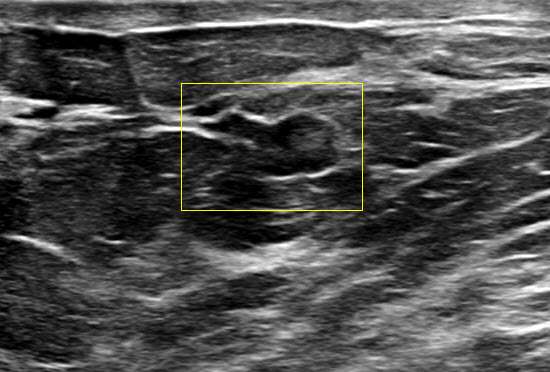

Case: Breast Ductal Anatomy and Function Figure 2

Figure 2: Ultrasound demonstrating a proteinaceous debris within a duct (arrow)